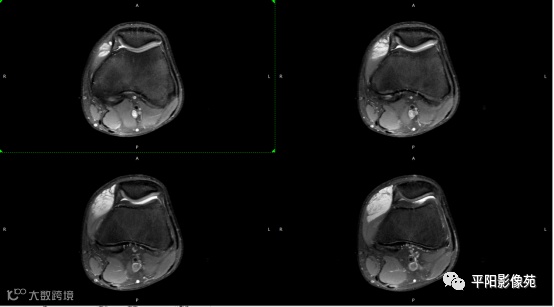

影像表现:

左膝关节股内侧肌内见多房样短T1长T2信号,内可见分隔,增强扫描明显强化,分隔未见明显强化,病灶局部与股骨远端分界不清。

MRI表现:好发于下肢, 较大病灶多为与肢体长轴一致的梭形, 边缘不清, 较小病灶呈类圆形, 边缘较清;②T1WI呈等或稍高信号, 病灶内部或边缘可见线条状或花边状高信号灶, 类似于皮下脂肪信号, T2WI上为明显高信号, 为本病特征性MRI表现;③病灶内静脉石及血管流空影为又一特征MRI表现;④GD-DTPA增强, 病灶明显强化, 其内低信号间隔无强化;⑤可见骨外形改变, 骨质增生及骨质吸收等表现。